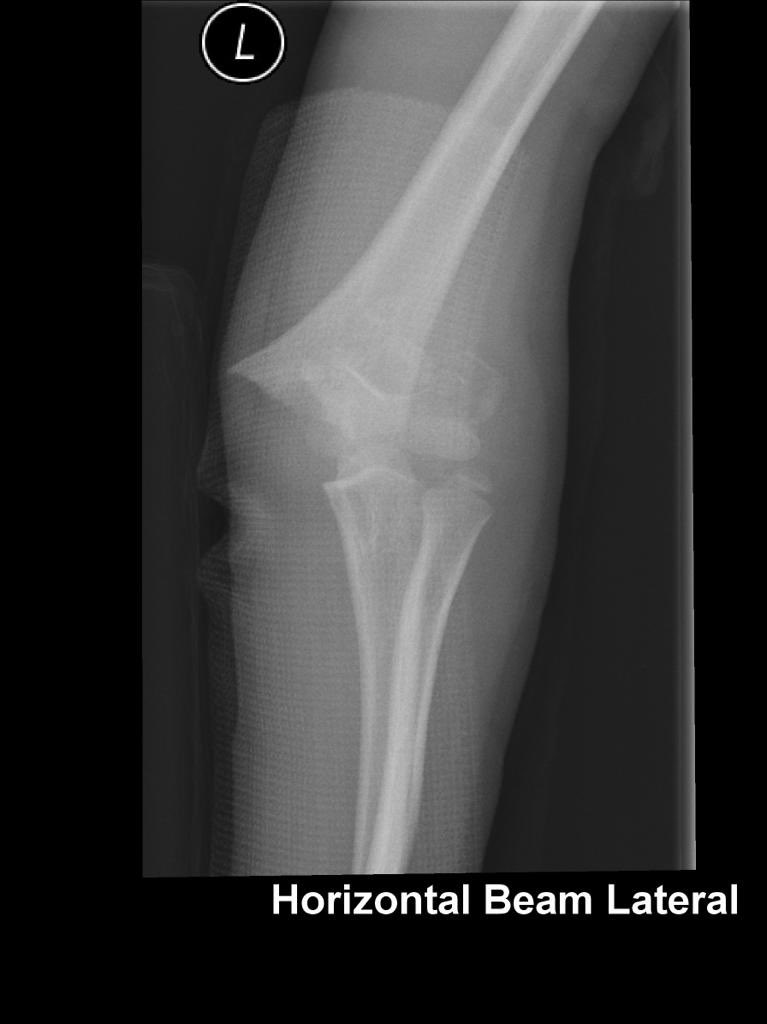

A little, flexible K-wire can do the trick! #Kapandji #BasicPhysics #LeverArm #PerCutaneousReduction #SupraCondylarFracture #MedTwitter #orthotwitter #OrthoTweetorial #SundayThoughts